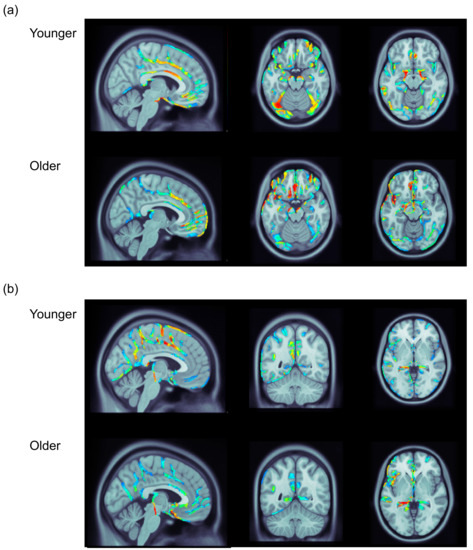

3.3. ERP Data: Distributed Source Analysis